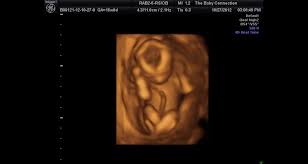

Baby connection roseville hours. The Baby Connection 4d 3d Hdlive Ultrasound Roseville. Im shocked it hasnt been reviewed before. You can feel confident in knowing that your ultrasound session will be provided by trained.

We are the proud providers of the most amazing ultrasound experience for our clients. Im shocked it hasnt been reviewed before. 267 reviews of The Baby Connection I cant believe that I had to add this business to Yelp.

3101 likes 6 talking about this 5666 were here. A unique 3D4D fetal ultrasound company offering Hd Live now. Ladies if you are looking for an affordable 3d4d ultrasound The Baby Connection is the place to go. The Baby Connection allows you to see what your baby looks like before they are born by the use of our state-of-the-art 3D4D and HDlive fetal ultrasound. 267 reviews of The Baby Connection I cant believe that I had to add this business to Yelp. 20 avaliações detalhes de contato e horário de funcionamento para The Baby Connection em 1211 Pleasant Grove Blvd Ste 100 Roseville CA. I started looking for an ultrasound place once my hubby and I found out he would be leaving for 2 12 months to Basic Training for the Air Force. The Baby Connection Inc. 246 customer reviews of The Baby Connection.

The Baby Connection Roseville CA. If you are looking for baby connection roseville hours simply check out our links below. Gender determination upon request. I started looking for an ultrasound place once my hubby and I found out he would be leaving for 2 12 months to Basic Training for the Air Force. A unique 3D4D fetal ultrasound company offering Hd Live now. The Baby Connections is a unique keepsake fetal ultrasound company that provides a mobile service as well as office visitsOur mobile service is the only service of its kind in our areaWe are located in Roseville California and we service Sacramento Placer and Sutter countyWe make all this possible for you by bringing you the Voluson i which is a portable. The receptionists both times were super friendly and455251.